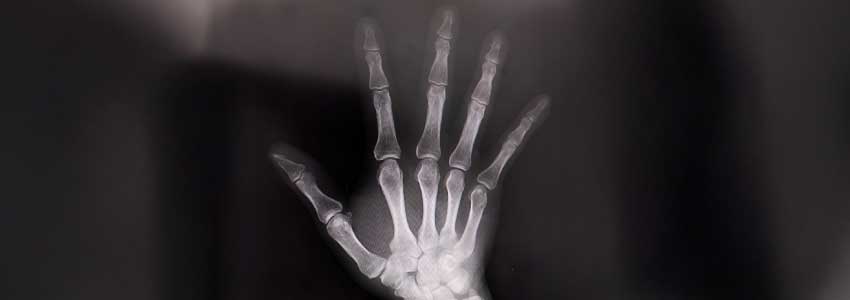

そこで、MRI検査を受け、自覚症状(右手を小指側に回すと痛みが増強する、クリック音がする)などからNさんは右手のTFCC損傷と診断されました。

すると、自賠責保険は、右手のTFCC損傷について、「MRI画像上損傷がはっきりしない」という理由で非該当の判断をしていることがわかりました。

その中で、画像上も自覚症状と整合する所見が見受けられるという話がありました。

その認定理由には、改めて画像を見たところ、「TFCC損傷」所見が認められると主治医の先生と同じ意見が書かれていました。